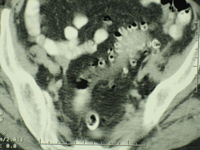

Diverticulose colique